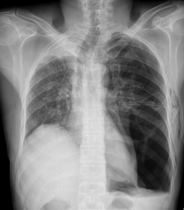

![]() |

Pneumothorax gauche de grande abondance./OpacitĂ© rĂ©ticulo-micronodulaire avec verre dĂ©poli de lâhĂ©michamp pulmonaire gauche avec individualisation dâune volumineuse bulle apical gauche./ | Pneumothorax droit de grande abondance./ OpacitĂ© rĂ©ticulo-micronodulaire dans lâhĂ©michamp pulmonaire droit, avec verre dĂ©poli et prĂ©sence d'une bulle apicale droite importante./ | Pneumothorax gauche modĂ©rĂ©./ OpacitĂ©s rĂ©ticulo-micronodulaires avec zones de verre dĂ©poli Ă©tendues sur lâhĂ©michamp pulmonaire droit./ | Pneumothorax bilatĂ©ral de grande abondance./ PrĂ©sence d'opacitĂ© rĂ©ticulo-micronodulaire avec aspect de verre dĂ©poli sur les deux hĂ©michamps pulmonaires, plus de grande bulle apicale sur le cĂŽtĂ© gauche./ SurĂ©levation de la coupole diaphragmatique droite avec trachĂ©e tirĂ©e vers la droite./ |